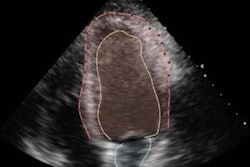

One of the most widely available modalities in cardiology, TTE is commonly used as a first-line screening tool as it's noninvasive and offers high temporal resolution, enabling low-cost clinical phenotyping, Jeong noted. However, the variations in probe position, acquisition length, breathing cycle, devices, and image quality require significant experience to interpret these TTEs, according to the researchers.

What's more, these images pose challenges for computer-vision algorithms for a variety of factors, including variations in image ratios, contrast, image acquisition, and equipment vendors, according to Jeong. As a result, Jeong and colleagues sought to address these challenges by developing an automated framework to first preprocess the images and then generalize, or standardize, the images prior to AI analysis.